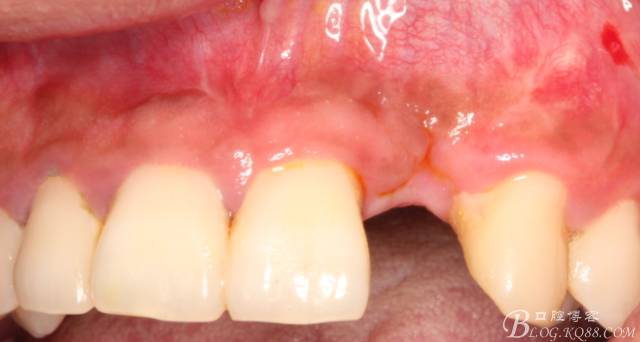

事實證明,我的做法沒有錯誤,一個月后,軟組織健康愈合。鄰牙軟組織沒有退縮。

4個月后,唇側(cè)豐滿度尚可,與鄰牙之間齦乳頭完整。